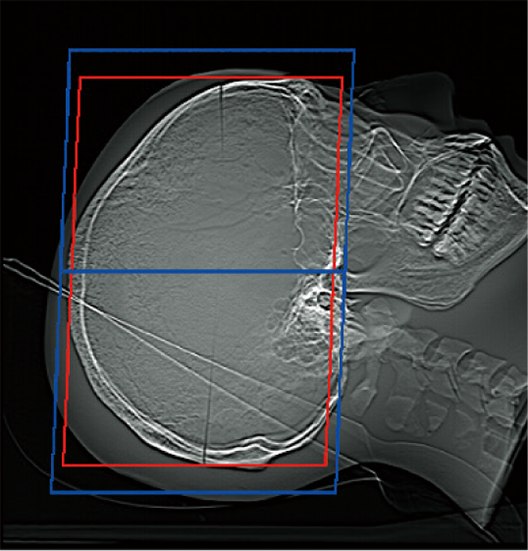

OM Line

SM Line Head

RB Line

Chest

Red: Position set automatically

Blue: Position set automatically + set margin